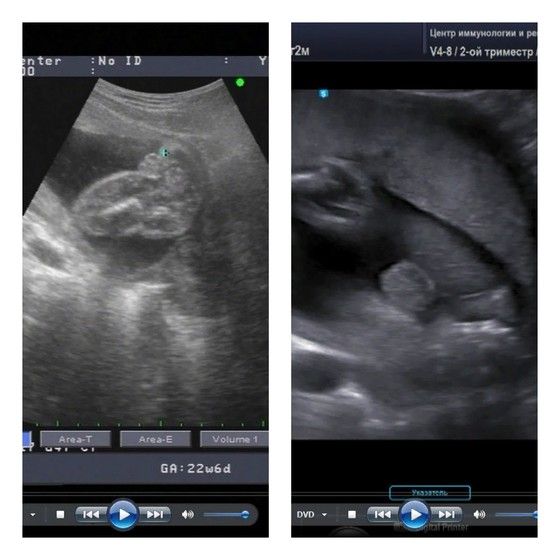

Сегодня был очень интересный и хороший день. Мы сходили на второй скрининг, ребёнок весь из себя здоровый и красивый, и тут узист говорит: "у вас 100% мальчик."

После этого заявления узист ещё раз 5 возвращался к гениталиям и показывал, приговаривая, что ошибки тут быть не может, всё чётко видно, и анализы эти ваши вам соврали)

И с сыном, и с дочкой говорили со 100% уверенностью пол - оба раза не ошиблись. А вы сами что на экране видели? Мне на втором скрининге как раз сына показали - ну никак не ошибёшься, настолько все выразительно 😅 с дочкой так же было, только раньше, в 15 недель - тоже все очень четко, явно девочка без вариантов. С кровью всё-таки вероятность ошибки, хоть и небольшая, но есть, особенно если называют девочку. Глаза не соврут, если на УЗИ все хорошо и чётко видно.

Чашка утреннего кофе, я вроде видела тоже всё очень ясно и четко. Лицо не так отчётливо можно было рассмотреть, как гениталии 😅

Дарья, малыш ноги развалил и вывалил свои неопровержимые доказательства прямо нам на монитор, фигурно выражаясь))

Слева дочь, справа сын. Примерно на одном и том же сроке.